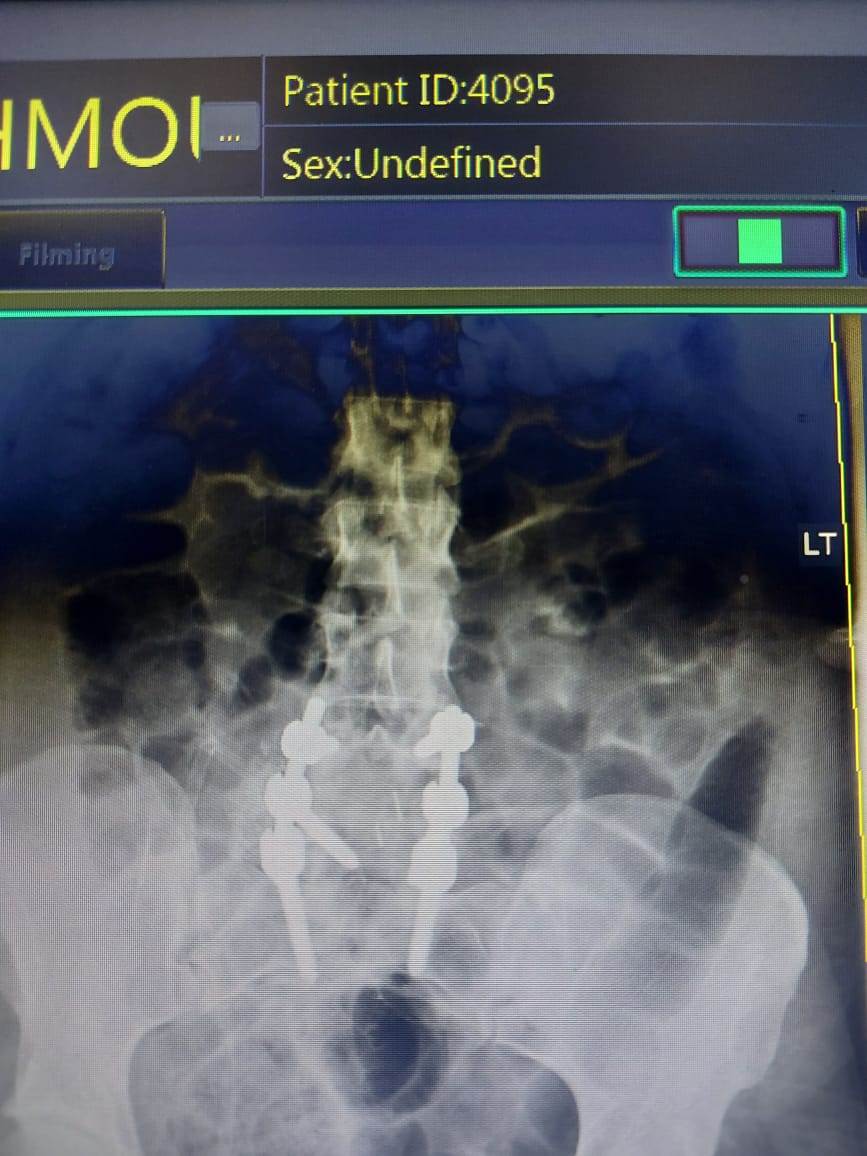

استحدث مستشفى المنيرة العام، خدمات طبية وجراحات جديدة، ولأول مرة أجريت فيه جراحة عمود فقرى، لمريضة تعاني من آلام مزمنة أسفل الظهر، ومنذ 3 أشهر زادت بطريقة شديدة، وتم فحص المريضة وعمل الأشعات اللازمة للتشخيص، وتشخصت بأنها حالة انزلاق فقارى قطني، بين الفقرات القطنية الرابعة والخامسة، والأولى العجزية، وهناك ضاغط علي جذور الأعصاب.

وعلى الفور تم استخراج قرار علاج علي نفقة الدولة، وإجراء جراحة توسيع للقناة العصبية، ومخارج جذور الأعصاب، وتثبيت للفقرات بواسطة أعمدة ومسامير، ودمج للفقرات بواسطة رقعة عظمية ذاتية، وقفص كربوني بين الفقرات القطنية الرابعة والخامسة، واستمرت الجراحة 3 ساعات.